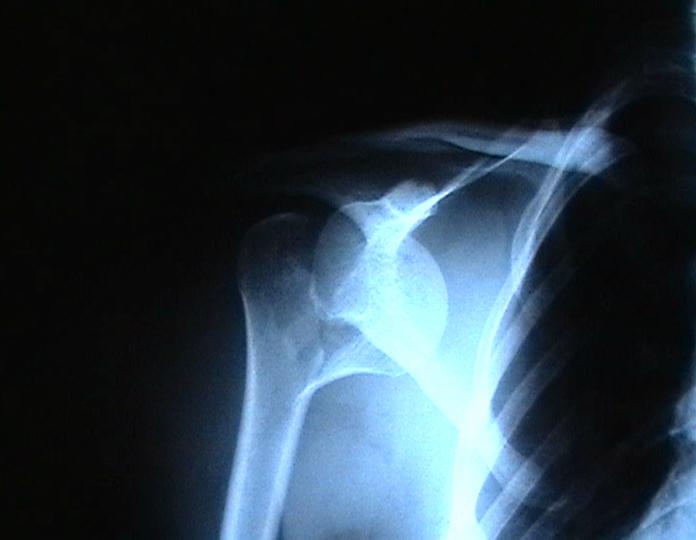

Re: Некроз головки плеча?

Согласен с вашим мнением -асептический некроз головки плеча. Есть ли у вас надежды на реваскуляризацию головки ? Если надеетесь, то имеет смысл продолжать физио, если нет, то следует думать опротезировании.

Переломовывих плеча сложная проблема и технически не уверен как для коллег, но для меня сколько я не встречался, технически сложно *вытянуть* вывихнутую головку из-под впадины. Последнее время не применяю пластины для фиксации перелома, а использую спицы и проволочную петлю (тем более часто и густо спонгиозные винты не держатся в головке прочно).